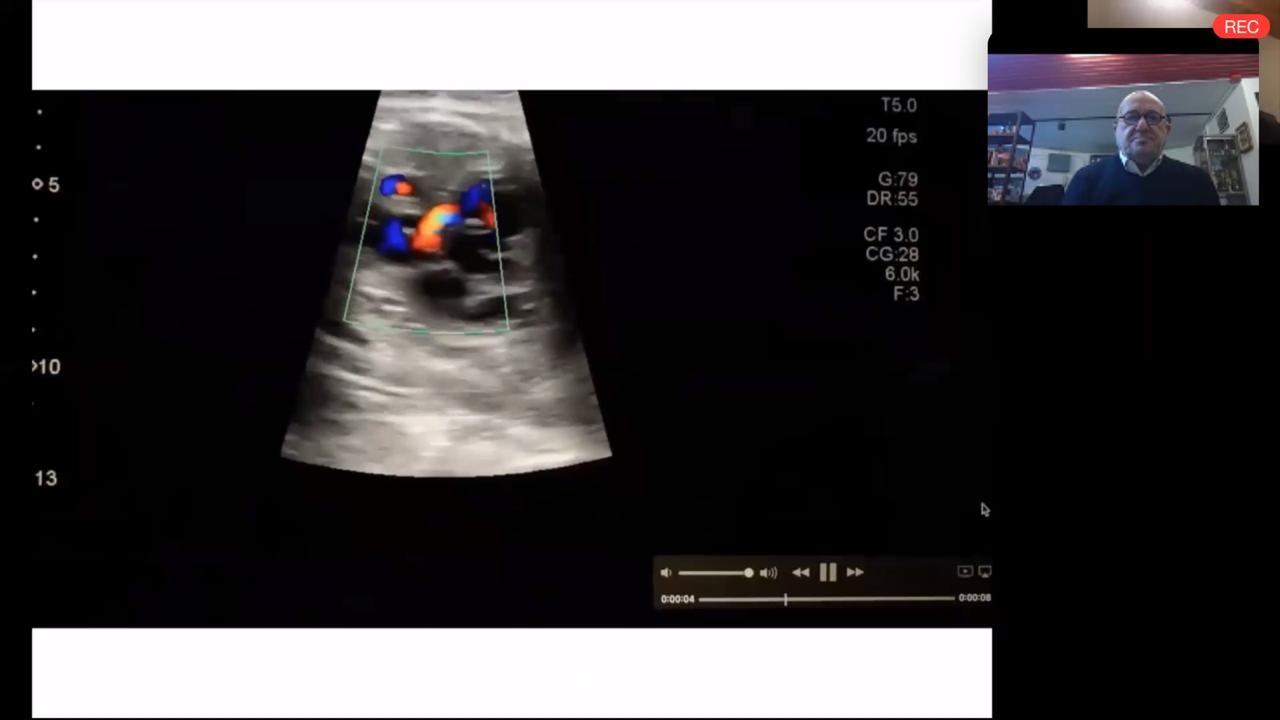

Auspiciada por Fundación Hospitalaria y organizada por la Fundación Cardioinfantil, el pasado jueves 23 de Julio se llevó a cabo una Master Class Online sobre Ecocardiografía Fetal.

Con una nutrida participación de más de 200 profesionales de diferentes países, la capacitación contó con las exposiciones del Dr. Pablo Marantz, Director Médico de Fundación Hospitalaria; y las Dras. Mercedes Sáenz Tejeira, Jefa de Cardiología; y Sofía Grinenco, integrante del servicio de Cardiología Fetal.

Las conferencias giraron en torno al diagnóstico prenatal de las cardiopatías congénitas, con la presentación de casos clínicos.